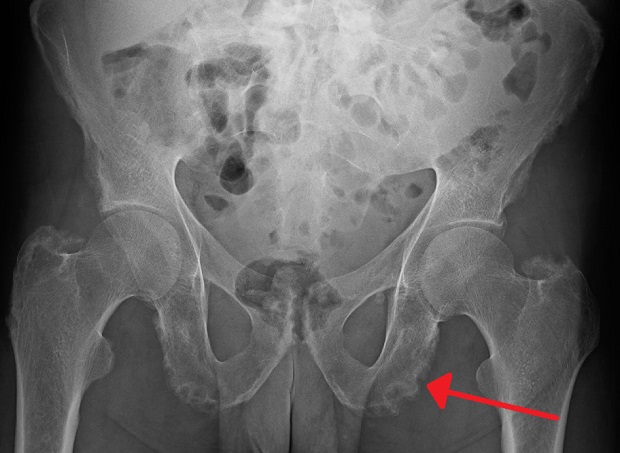

Диагнозата ентезопатия, неуточнена, се поставя след снемане на подробна анамнеза и извършване на щателен физикален преглед. Осъществяването на някои лабораторни и образни изследвания, като рентгенография, ядрено-магнитен резонанс, компютърна томография, ехография и други, спомагат за допълнително уточняване тежестта на уврежданията и тяхната локализация.

Изображение: James Heilman, MD, CC BY-SA 4.0, via Wikimedia Commons